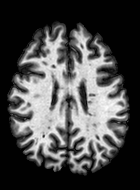

Patch size is another important parameter of the network. In computer vision applications such as object detection, usually a whole 2D image is used as a feature. However, full 3D medical images can not typically be used because of memory limitations. Fig. 4 shows examples of lesion memberships obtained with different sized 2D patches. As the patch sizes increases, the false positives that are mostly observed in the cortex tend to decrease. Fig. 5 shows a plot of Dice and LFPR with various patch sizes, ordered from left to right according to their increasing size. Note that smaller patches ( to ) produced significantly lower Dice and higher LFPR compared to other patches (), as seen from the memberships in Fig. 4. Also some of the highest Dice and lowest LFPR were observed for patches with large in-plane size, i.e., , , and . It was observed in Fig. 5 that there is no significant difference between Dice coefficients for , , or , but LFPR of both and are significantly lower than that of (). We chose as the optimal patch size. Other choices of smaller and patches (not shown) yielded worse results. Note that although training was performed with different patch sizes, the memberships were generated slice by slice, as the trained model consisted only of convolutions and did not need any information about patch sizes.

In our experiments, we used large 2D patches similar to Ghafoorian et al. (2017b), in comparison to isotropic 3D patches as used before, e.g., in Valverde et al. (2017), in Wachinger et al. (2017), and in Kamnitsas et al. (2017). The rationale behind using large anisotropic patches is twofold. First, experiments with full 3D isotropic or patches showed little or no improvement in Dice and led to increased false positives, with memberships similar to the one with patches, as shown in Fig. 4. Larger isotropic patches, e.g. or , showed inferior segmentation, and in some cases, optimization did not converge. The reason is that the FLAIR images in the test datasets had inherently low resolution in the inferior-superior direction, mm and mm compared to in-plane resolution of mm. Therefore 2D axial patches capture the high resolution in-plane information that represents the original thick axial slices. Second, the lesions are usually focal and small in size, unlike other brain structures. Therefore a very large isotropic patch around a small lesion can include superfluous information about the lesion, which can increase the amount of false positives. Note that with in more recent studies employing high resolution 3D FLAIR sequences, it is trivial to extend the algorithm to accommodate for 3D patches.